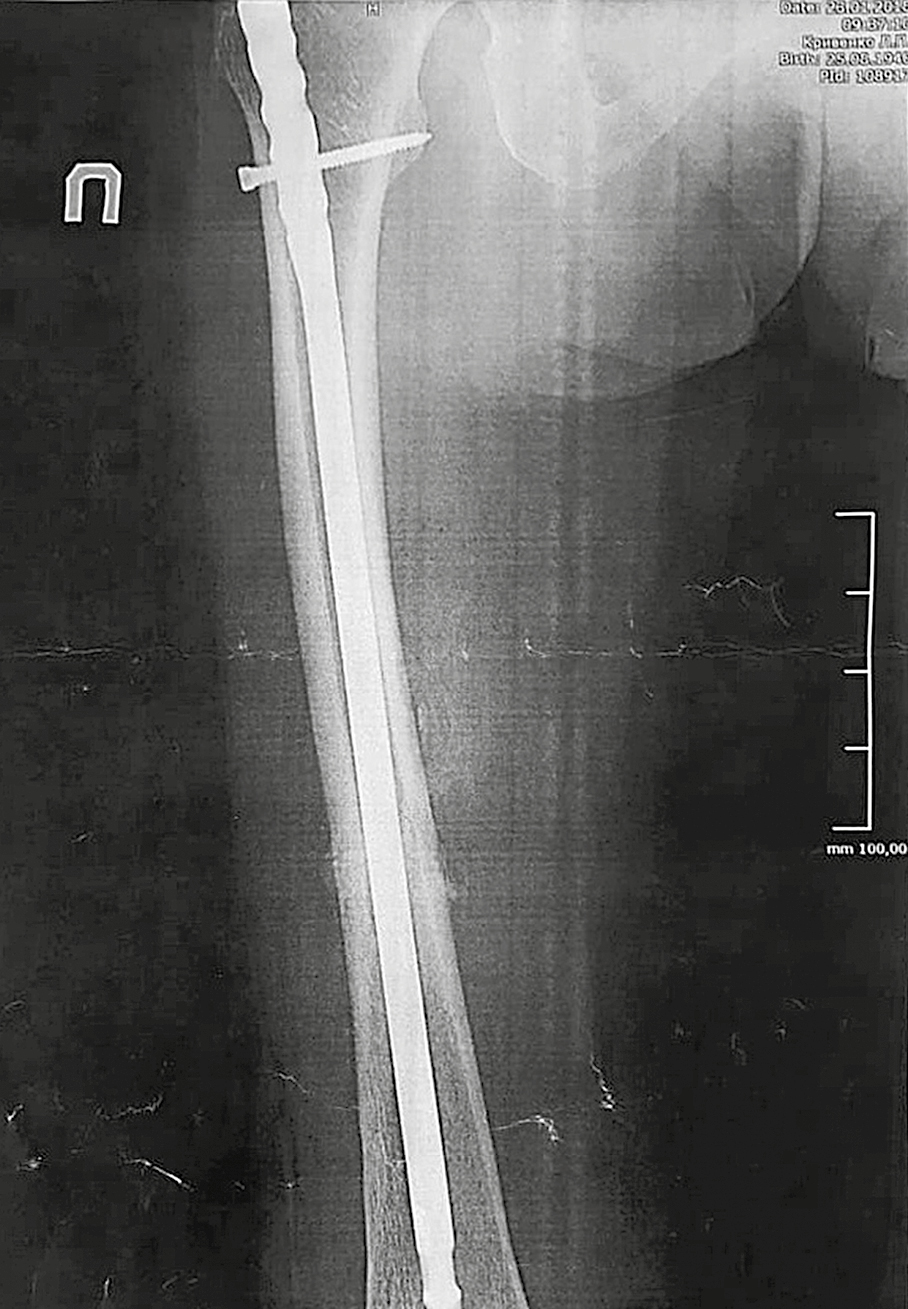

A 78-year-old woman, receiving oral bisphosphonate for severe postmenopausal osteoporosis for 3.5 years, suddenly started feeling pain in her right thigh while walking. Three months later, she had got a fracture in middle third of the right femur after falling from her standing height. According to instrumental diagnostics, this fracture had all criteria of AFF. Blocking intramedullary osteosynthesis with shafts was performed. A retrospective analysis of soft tissue magnetic resonance imaging in the area of right thigh, done before the fracture, showed the presence of undiagnosed incomplete right femur fracture in the middle third, which subsequently led to a complete fracture.

3. Fig. 3. Radiograph of the right thigh of patient K. 8 weeks after the intramedullary osteosynthesis of the femur with a pin with a blocker, dated January 26, 2018.

Subject

Type Other

View (570KB)

Indexing metadata ▾